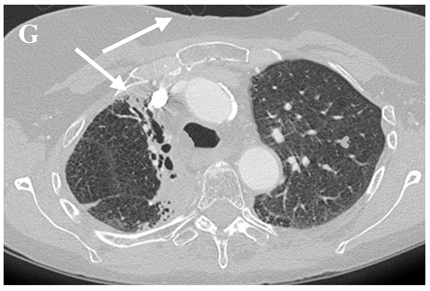

6.4.2. Chest CT-Scan

In the event of worsening symptoms after empirical antibiotics, Chest CT may provide more insights. Interestingly, the opacification lines in both X-ray and CT conform to radiation port rather than anatomical lines of lung structure, which could be diagnostic. Identified progression outside the lung field might suggest immune-mediated lymphocytic alveolitis [72]. Various stages of presentation provide different imaging outlooks (Table 3).

During the acute exudative stage, features of ground-glass attenuation or homogeneous consolidation may be noticed. A patchy consolidation that confirms the irradiation portal is also suggestive of the early phase. A discrete consolidation that conforms to the shape of the irradiation portal is proliferative changes of irradiation [71].

A chronic fibrosis stage with features of parenchymal distortion, traction bronchiectasis, and pleural thickening resulting in volume loss and irreversible changes are noticed. Refer to Table 2.